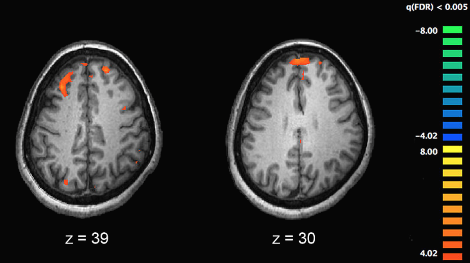

사람마다 다르겠지만, 많은 분들이 이런 어려운 학문에 대한 경외심을 가지실거라 생각합니다. 심지어 많은 학자들 또한 비슷한 반응을 가집니다. 이에 대해 학계에서는 뇌영상 편향 (Neuroimage Bias)이라는 단어까지 등장합니다. 뇌만 나오면 모두 두려워하고 대단한 것으로 여기는 문제인 것이죠. 물론 신경과학은 정말 복잡하고 새로운 학문이 맞다고 생각합니다.

뭔지 모르겠지만 그냥 어렵고 대단해보인다